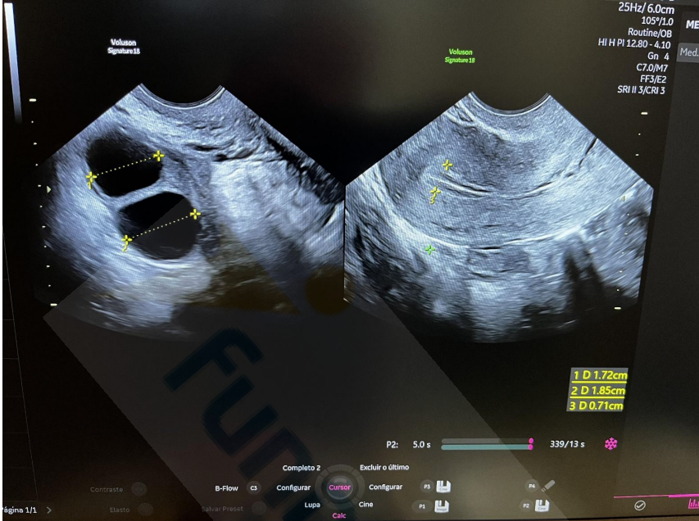

Analise a imagem abaixo de um exame de ultrassonografia transvaginal.

Considerando a análise desse exame, a paciente:

I. Está no período periovulatório.

II. Pode estar realizando estimulação ovariana.

III. Está em uso de contraceptivo hormonal combinado.

IV. Pode estar com muco cervical aumentado pela fase do ciclo em que se encontra.

Quais estão corretas?